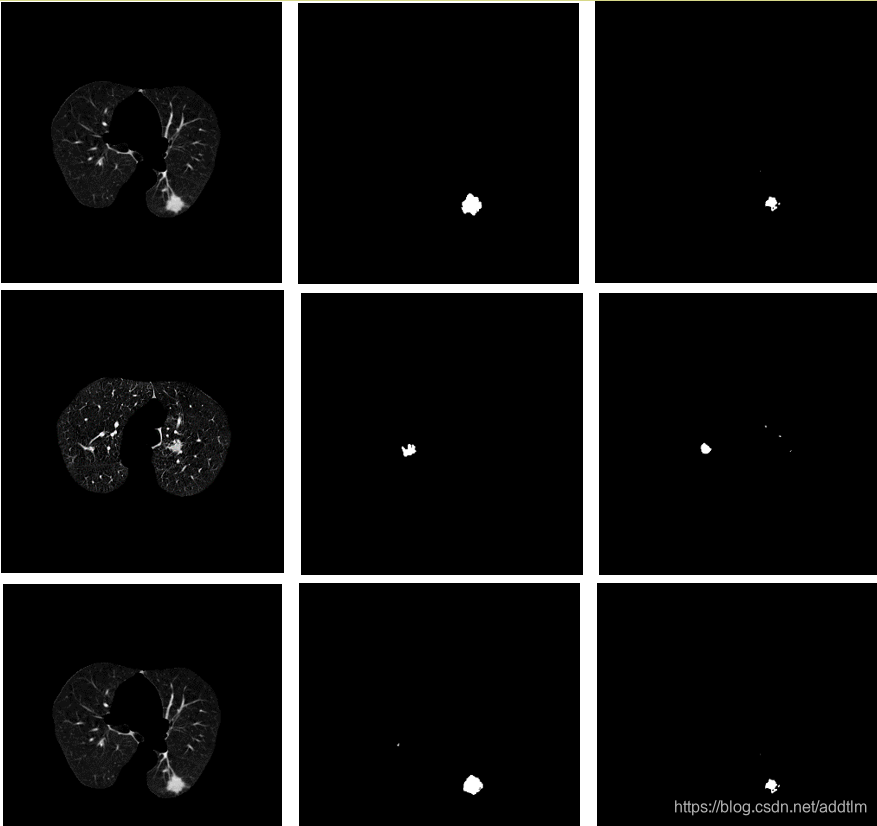

肺结节提取网络效果如下: